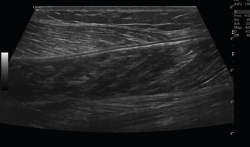

Su indicación fundamental es en el diagnóstico de las lesiones de partes blandas superficiales.

Las estructuras específicas más adecuadas para este estudio incluyen tendones, músculos y ligamentos, además de masas periarticulares de tejidos blandos. Es útil para el diagnóstico de derrame articular, engrosamiento sinovial, bursitis, cuerpos libres intraarticulares, gangliones, quistes, roturas ligamentosas y tendinosas, tendinitis y fracturas ocultas(6).

En el estudio musculoesquelético se utiliza una sonda lineal con alta frecuencia, de entre 9 y 13 mHz.

Tanto el ligamento lateral interno (LLI) como el ligamento lateral externo (LLE) pueden ser valorados por ecografía (Figura 7).

Figura 7. Corte coronal de una ecografía de rodilla. A: engrosamiento del ligamento lateral externo en la inserción proximal por un esguince de grado I; B: engrosamiento del ligamento lateral interno.